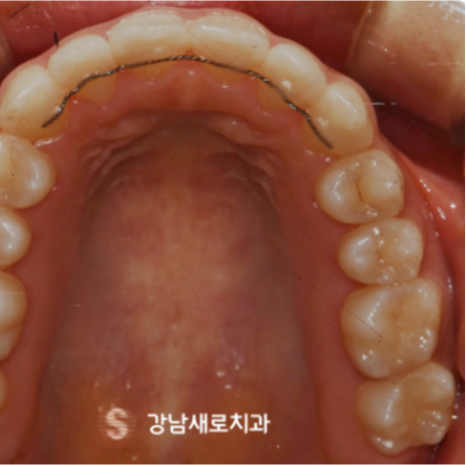

다음은 비발치교정 치료를

진행 한 후 촬영한 모습인데요.

작은 어금니를 발치하지 않은

상태에서 교정을 진행하게 되면,

위 사진에서 표시한 것과 같이

어금니를 포함한 모든 치아를

뒤쪽으로 이동시켜야 하기 때문에

어금니의 교합이나 위치에도

당연히 변화가 발생한다고 했어요.